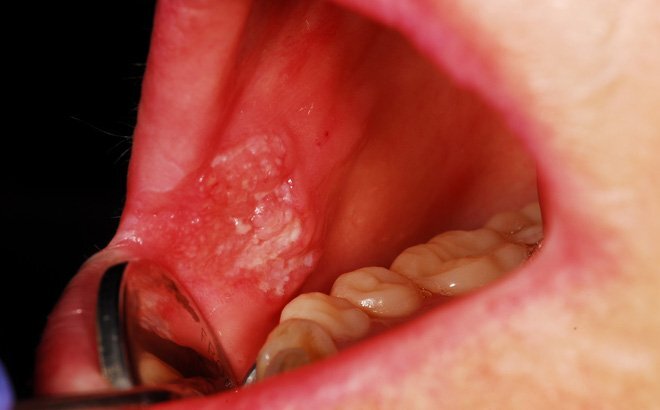

Triệu chứng thường gặp của ung thư miệng khá giống với những bệnh lý răng miệng khác, bạn hãy đi khám nếu có những dấu hiệu dưới đây.